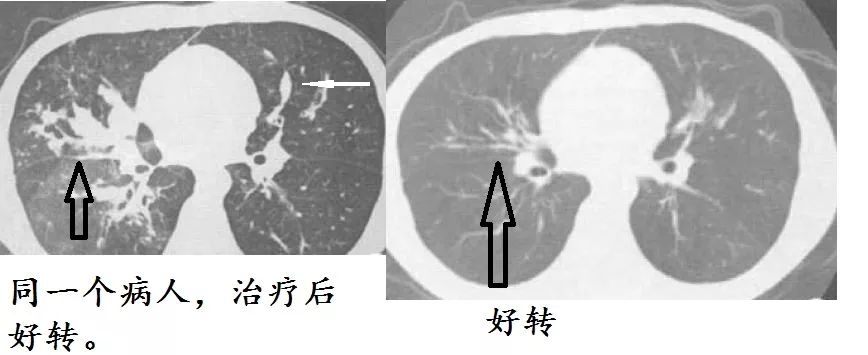

确诊变应性支气管肺曲霉病,给予糖皮质激素及伊曲康唑口服液治疗。6个月后复查,病灶好转,支扩好转,症状好转,全部都好转。